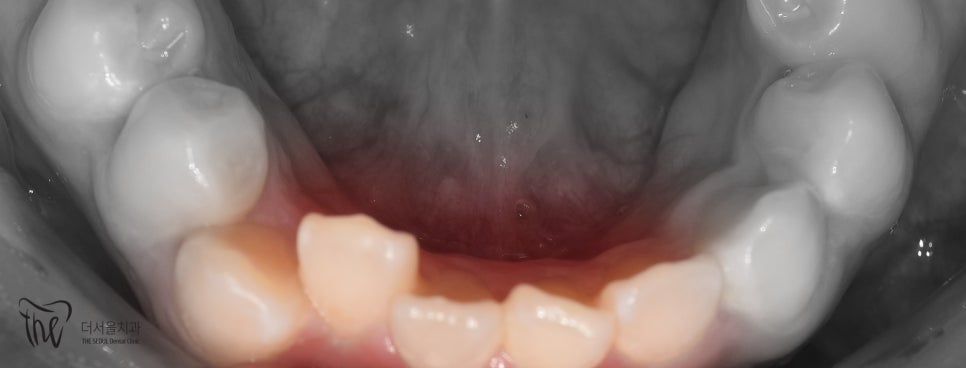

사진을 보면

*측절치에서 왜소치 가 관찰되고 있었으며

아랫니가 윗니를 덮고 있는 반대교합을 보였습니다.

측면에서 바라보면

송곳니가 튀어나온게 두드러졌으며

치열이 고르지 못하고

삐뚤빼뚤 한 것을 볼 수 있었습니다.

정리해 보면

- 12번 [측절치] = 왜소치

- 앞니 삐뚤거림이 관찰되고 있었으며

이로 인해

- 이 사이 공간이 생길 수 있고

- 앞니 크기 불균형으로 이어질 수 있습니다.